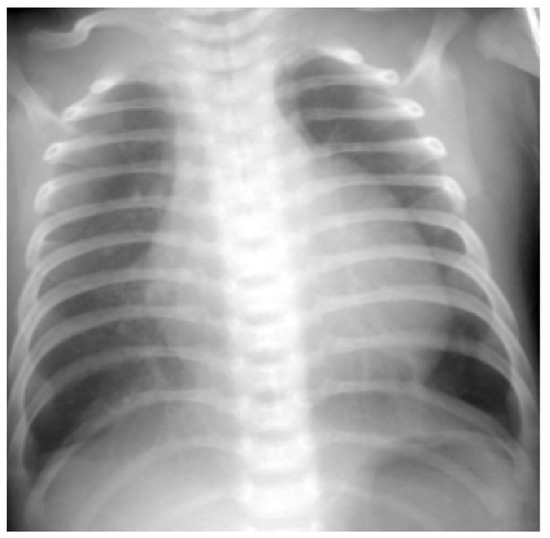

3.3. Case 3

3.4. Case 4